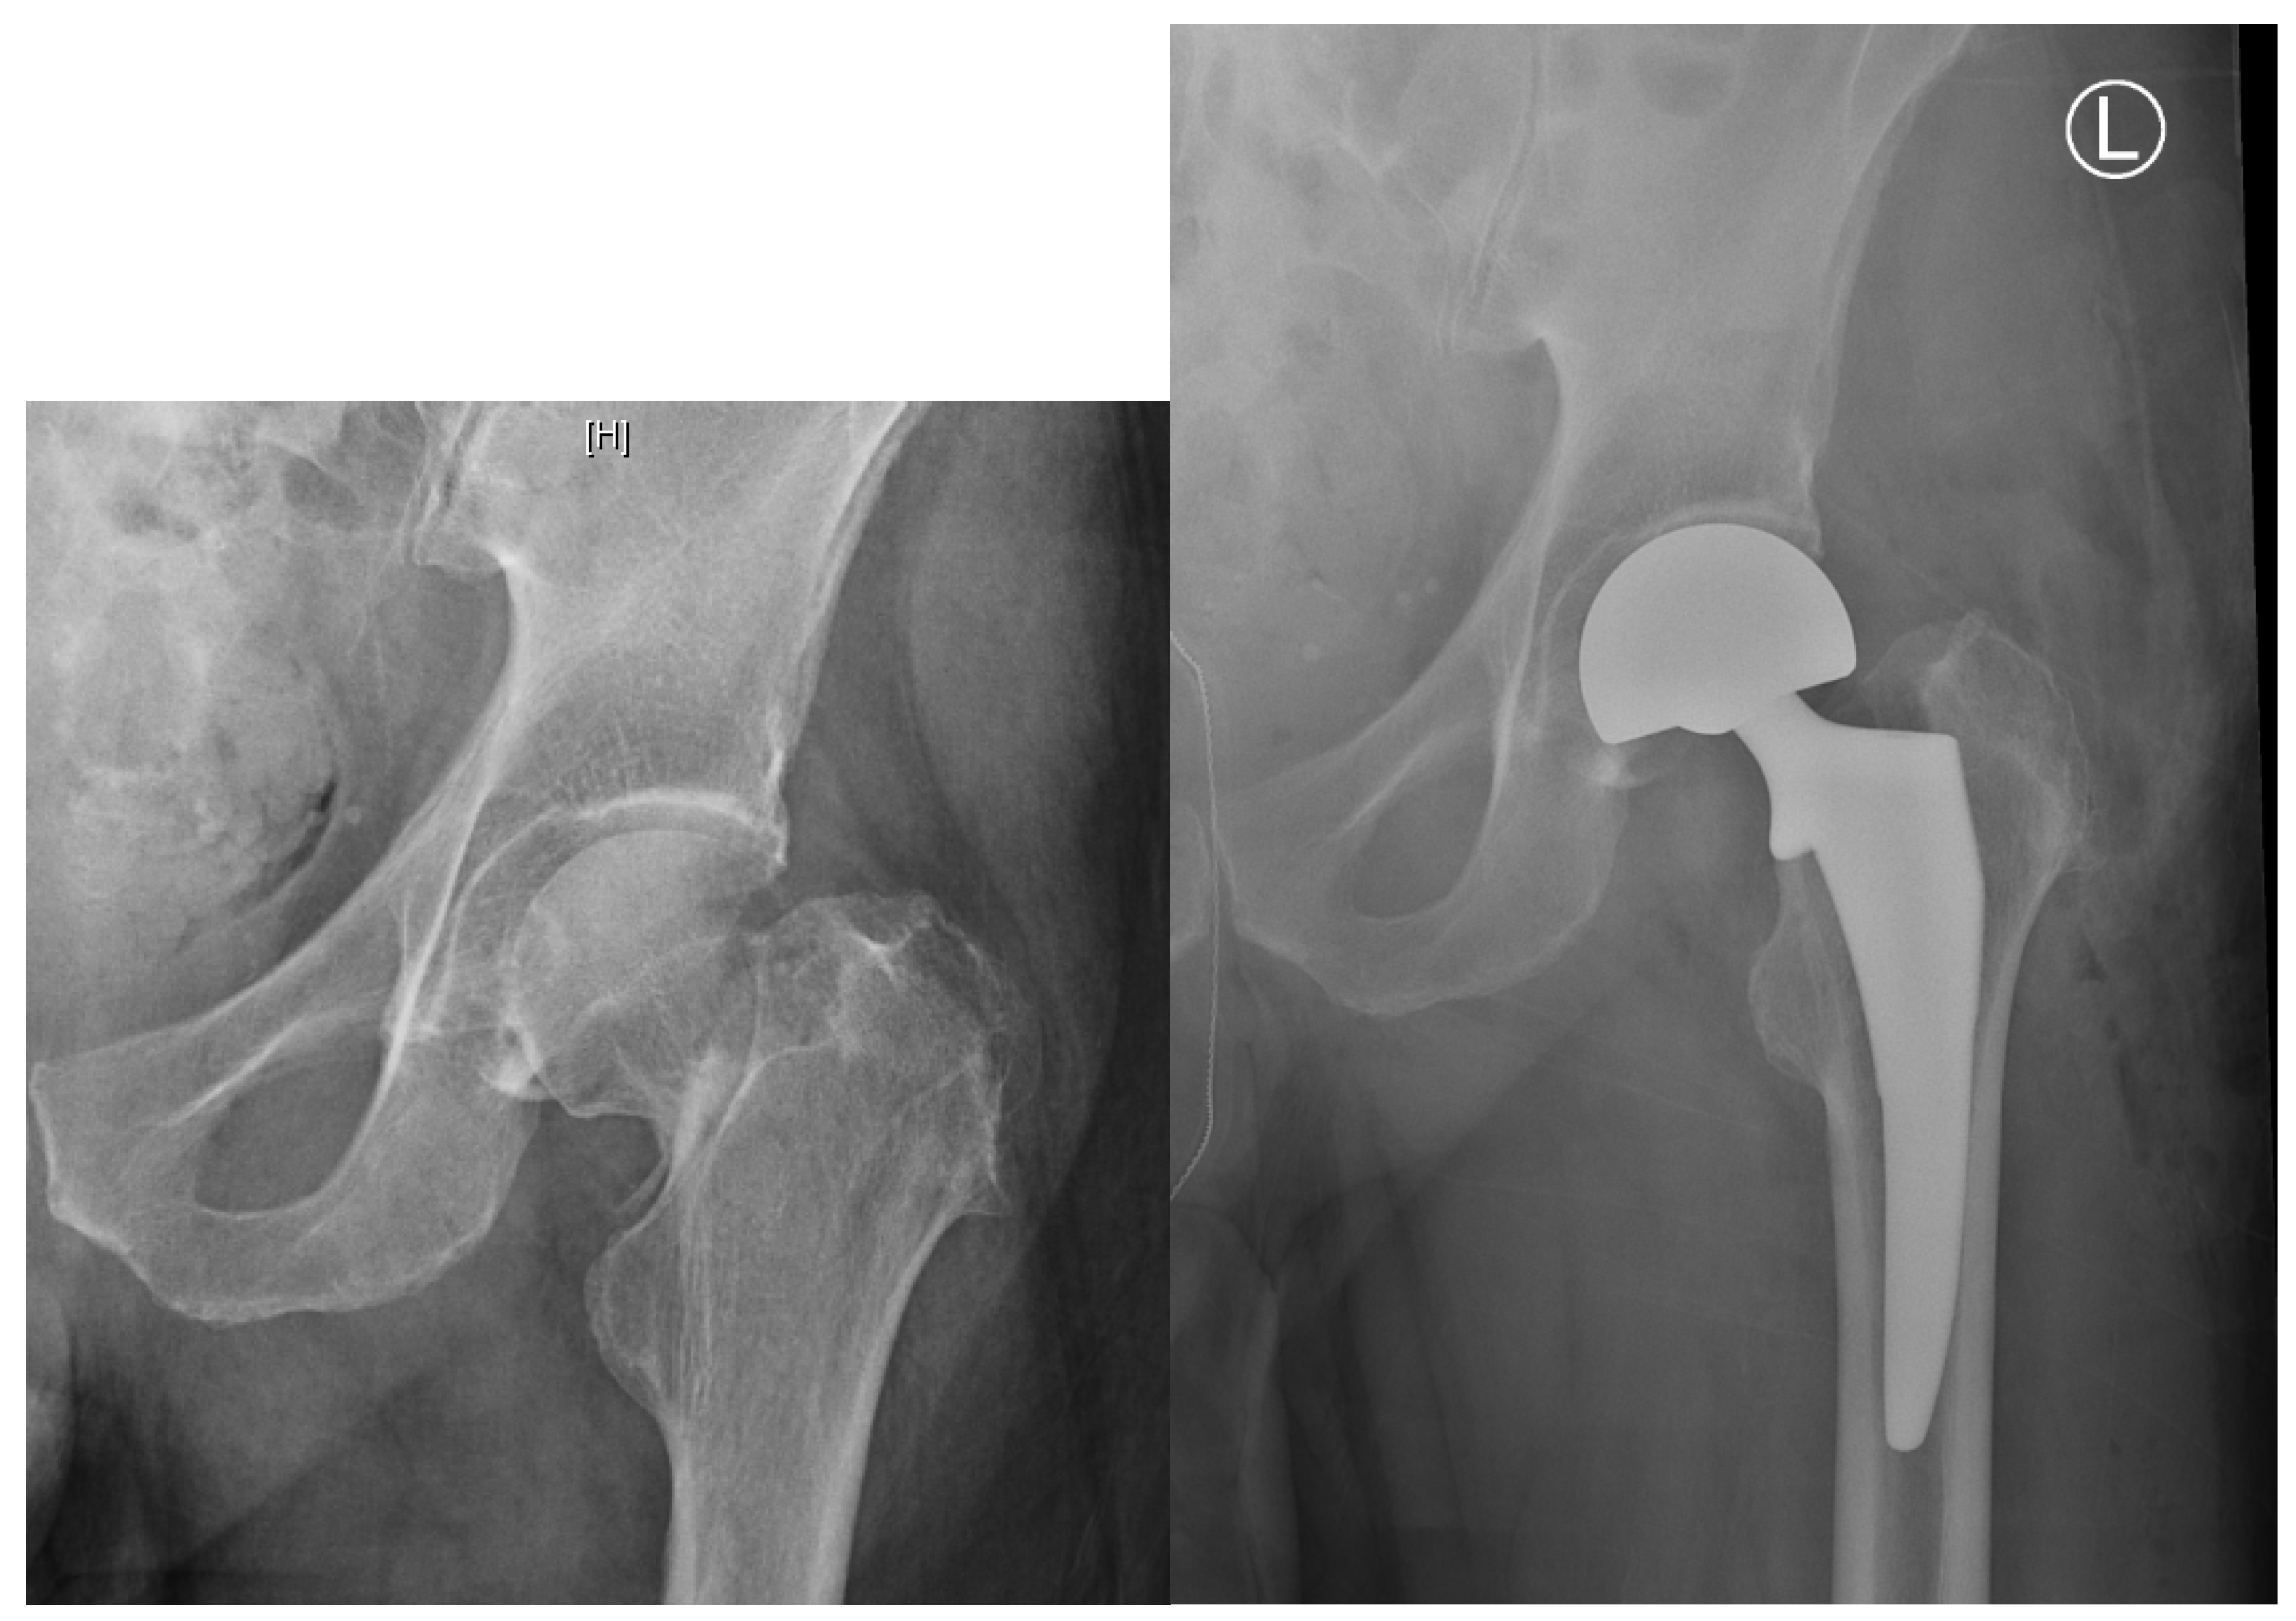

2.3. Displaced Femoral Neck Fractures: Internal Fixation vs. Arthroplasty

2.4. Displaced Femoral Neck Fractures: Hemiarthroplasty vs. Total Hip Arthroplasty